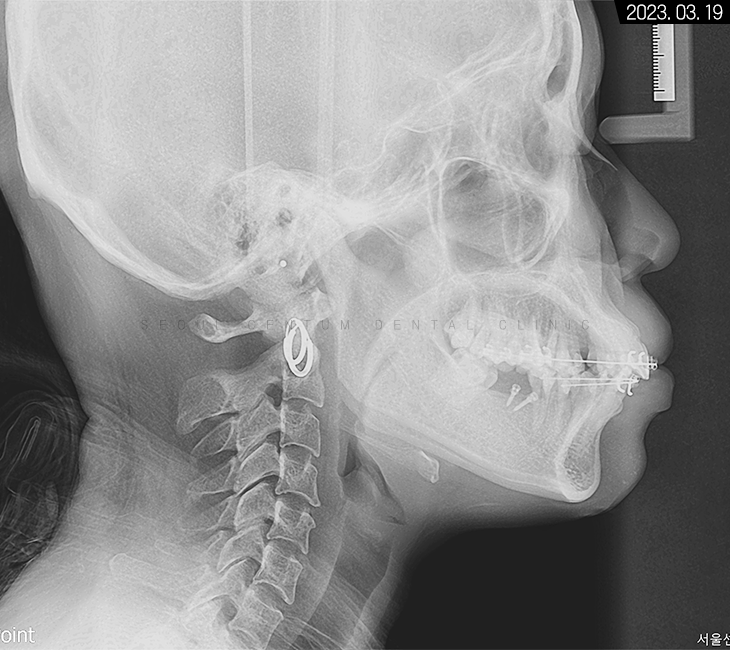

세팔로 사진으로는

잇몸과 치아 전돌 양상이 보이고

에스테틱 라인을 과하게 넘어가 있다는 것을

알 수 있었습니다.

계측점을 분석해 본 결과 정상 범주로 넣기 위해서는

치아 후방 이동이 상당히 필요한 경우였습니다.

뻐드러진 앞니 모양이 보이는데,

이 같은 상태면 앞니 사용이 좋지 않아

식사가 불편하고 아랫니가 잇몸을 자극해서

치주염까지 생길 수 있어 주의해야 합니다.

전면으로는 골격 비대칭 양상도 보여

다방면을 고려한 맞춤 치료를 진행하기로 했습니다.